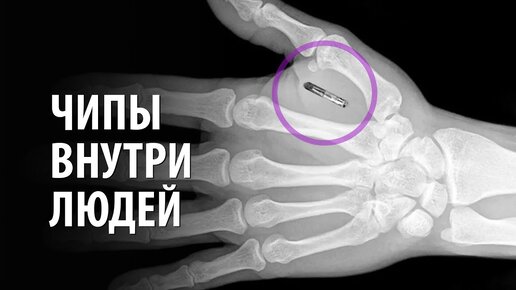

Чипирование людей как повлияет чипизация населения؟ Про память человека